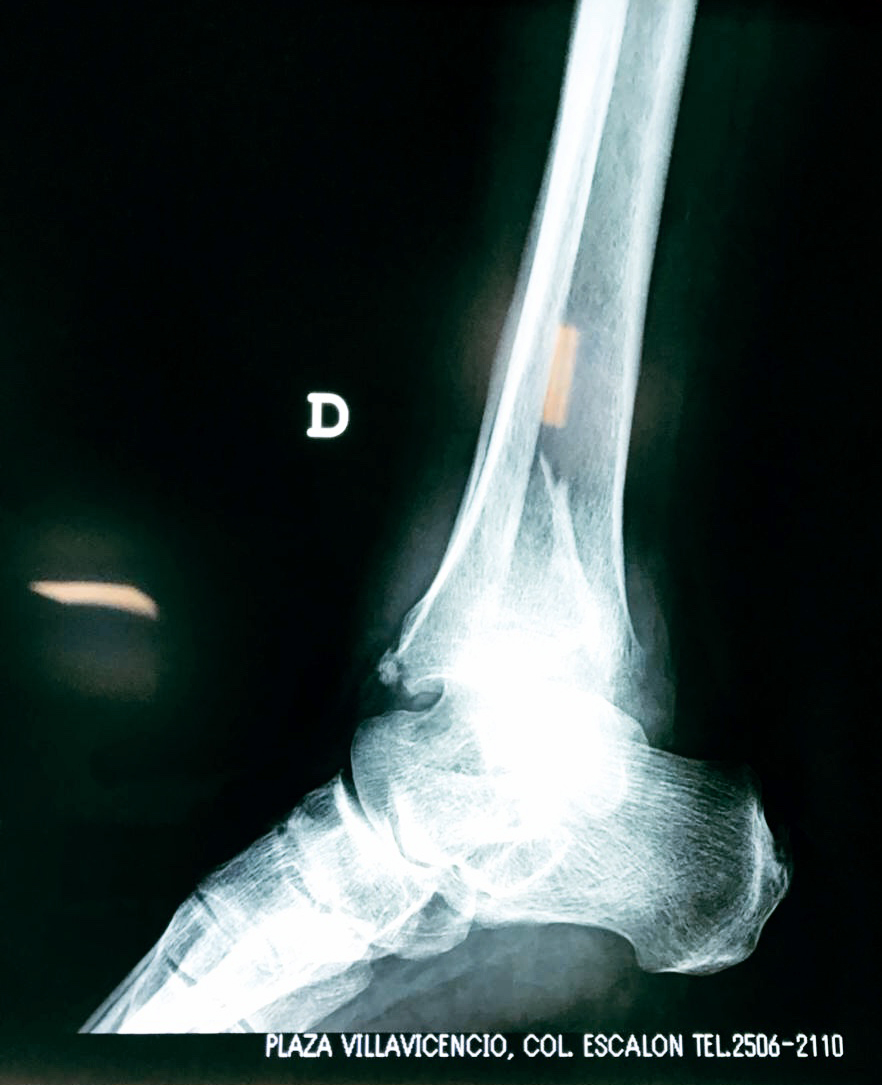

Una fractura de tobillo es la rotura de uno o más de los huesos del tobillo. Estas fracturas pueden ser:

- Completas (el hueso está perforado y está en 2 partes).

- Los extremos de los huesos están desalineados entre sí (desplazados).

- La fractura se extiende hasta la articulación del tobillo (fractura intra-articular).